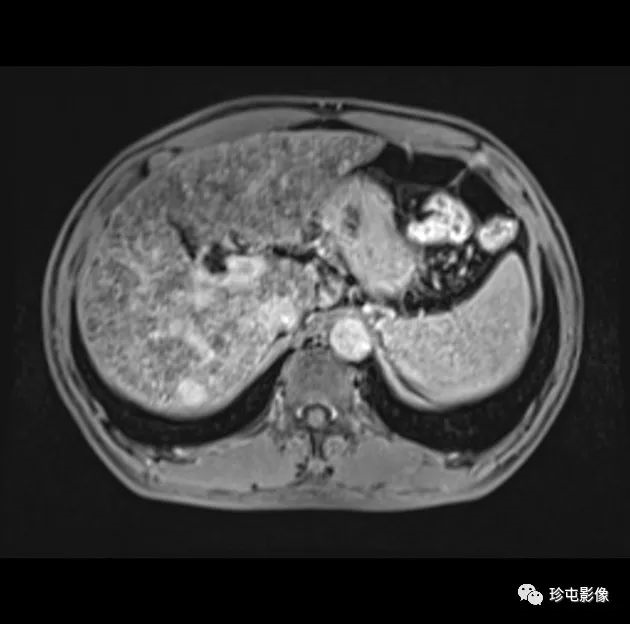

肝细胞癌(HCC)可分为增殖性和非增殖性,这可能对常规经动脉化疗栓塞(cTACE)后的结局有影响。cTACE前常规不进行活检以识别增殖性HCC。

|  | |

共计1,194例患者(男性1,021例;平均年龄54岁±12岁(SD);中位随访时间为29.1个月)。该预测模型名为SMARS评分,包括分叶状形态、马赛克结构、甲胎蛋白水平、动脉期边缘高增强和卫星病灶。在训练组和验证组中,SMARS评分的受试者工作特征曲线下面积分别为0.83和0.80。根据SMARS评分,预测增殖型hcc患者(n = 114)的肿瘤缓解率较低(48% vs 71%;P & lt;.001)和更差的PFS(6.6个月对12.4个月;P <.001)和OS(14.4个月对38.7个月;P <.001)高于非增殖性肝癌(n = 263)。【Yan Bao 2023 】

该预测模型具有较好的鉴别增殖性hcc的性能。根据SMARS评分预测增殖型肝癌患者cTACE术后预后较预测非增殖型肝癌患者差。

肝癌的组织病理

SMARS 评分

- S shape of the tumor (肿瘤形状)

- M mosaic architecture (马赛克结构) 【】

- A stands of AFP level (AFP水平)

- R rim APHE (边缘APHE)

- S satellite lesion (卫星病变)